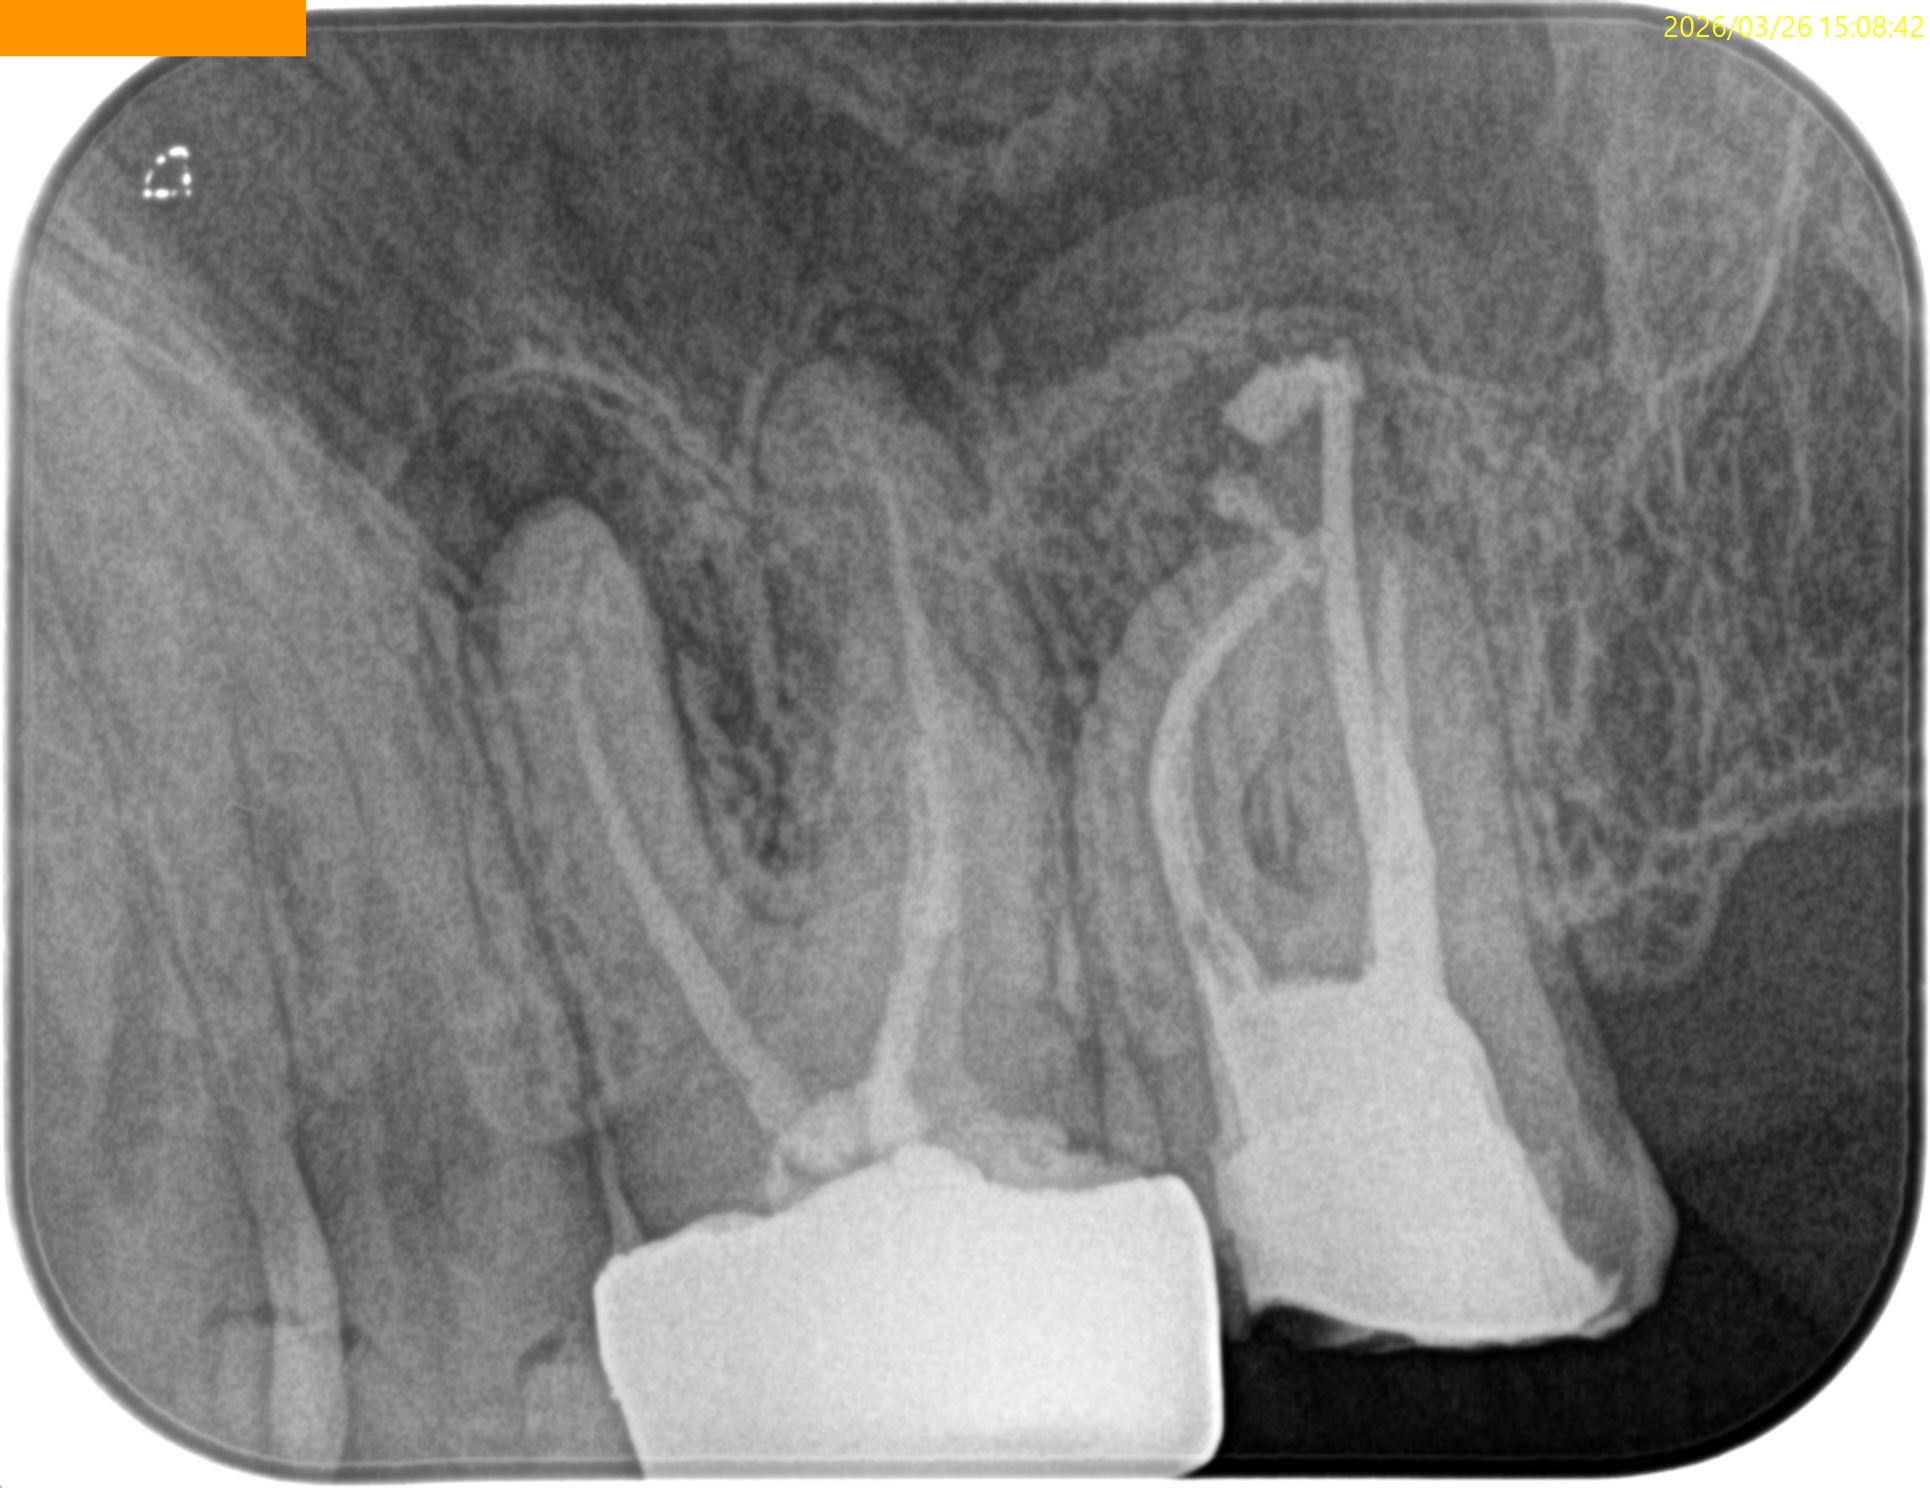

まず第2大臼歯から。

MB

MB2

DB

P

複数根管があるのはMBであるが、

これらの絵だけで合流しているか?否か?がわかるだろうか?

またMB2は見つかるだろうか?

その際は、

この辺りを探索する必要があるだろう。

短針でスカウティングする際に、掴めるポイントは全て突いた方がいいだろう。

どこが本当のMB2の入口か?判別できないからだ。

またMB2の多くはMB1と合流するという臨床的事実から形成済みのMB1に当該Gutta Percha Pointを挿入しMB2にFileを入れてグリグリとやってみた。

すると…

13.5mmの地点に傷がついていることがわかる。

ここが合流地点だろう。

これで以下のように作業を行った。

MB2は狭窄根管だがMB1と合流しているので13.5mmとして形成した。